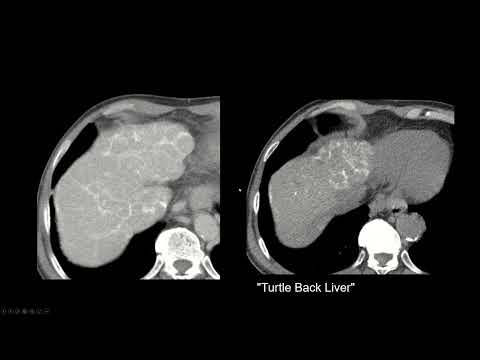

Вы стажёр-рентгенолог? Ознакомьтесь с нашей полной библиотекой случаев, чтобы быть готовым к дежурству, здесь: КТ коронарных артерий с определением кальция может помочь вам снизить риск инфаркта миокарда... но не так, как думает большинство. Стоит ли всем её делать? Нет. Стоит ли вам? Это зависит от ситуации. Приношу извинения за некоторые проблемы со звуком. Видео доктора Раджеша Бхаяны. Все мнения принадлежат мне. Особая благодарность доктору Джайдипу Халанкару, кардиоторакальному рентгенологу, за его помощь. #коронарныйкальций #КТ #рентгенология #кальций #сердечно-сосудистый #риск #ишемическаяболезнь Схемы коронарных артерий: ; Изображение: brgfx на Freepik Видео о боли в груди: